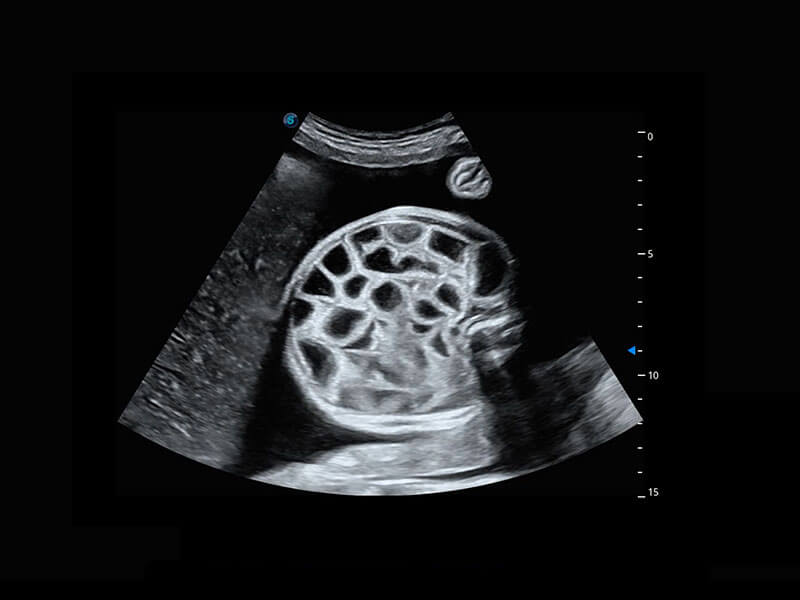

腔内三维-宫内节育器

腔内三维-光影成像